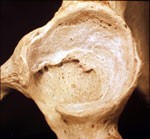

artrosi foto